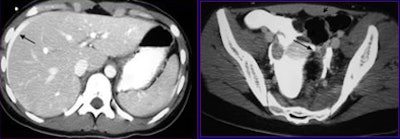

| A 35-year-old woman after a motorbike collision with pelvic impact. Initial axial CT scan (left) shows high-attenuation perihepatic fluid (arrow). Five-minute delayed scan (right) demonstrates bladder dome rupture with clot covering (arrow) and contrast material extravasation in the intraperitoneal space (arrowheads). The patient subsequently underwent bladder repair. |